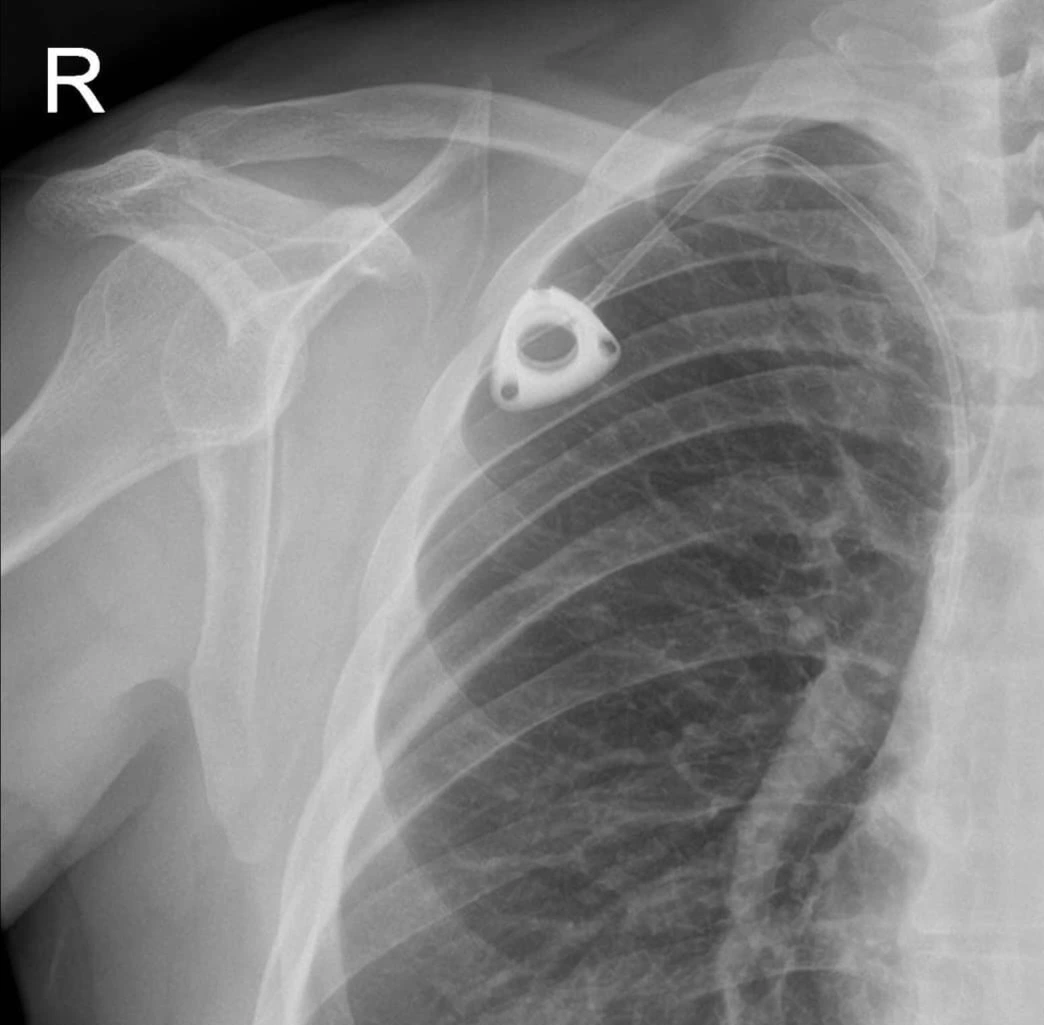

둘째날 첫 일정이 케모포트 시술이다. 독한 항암약을 투여할 경우 팔에 맞는 혈관 주사는 위험하고 피부 괴사등의 부작용이 있어, 케모포트라는 장치로 항암약을 주사하는 보다 효과적인 방법이다. 케모포트는 목에서 심장으로 들어가는 정맥에 호스를 연결해서 항암제를 투여하는 방법으로써 항암의 Chemotherapy와 연결의 Port가 어원인 합성어인듯 보인다. 적적한 한국말을 찾지 못해 그냥 사용하나 싶다. (미국에서는 키모포트라고 발음하기도 한다.)

시술은 대충 15분 정도 되었는데, 대충 기억하는 바는 다음과 같다. 마취주사를 여러번 놓고, 바로 칼로 피부를 두군데 절개하고, 아래쪽 절개면에 이내 케모포트를 삽입하는게 느껴졌다. 자리를 잡은 케모포트에서 연결 호스만 위쪽 절개면으로 뽑아내고, 위쪽 절개면에서 정맥을 찾아 구멍을 내고, 케모포트의 호스를 정맥 구멍으로 깊숙이 집어 넣었다. 뭔가가 심장 깊숙이 들어오는 느낌에 나도 모르게 ‘크억’하는 호흡을 하였다. 호스가 잘 동작하는지 테스트하기 위해 주사바늘을 케모포트에 장착하고, 서너번 주사액을 주사했다. 잘 자리잡았는지 케모포트를 잡고 흔들어보더니 두 절개면을 봉합하면 시술이 끝났다.

케모포트가 달린 나의 X-Ray: 캐모포트와 호스가 같이 보인다